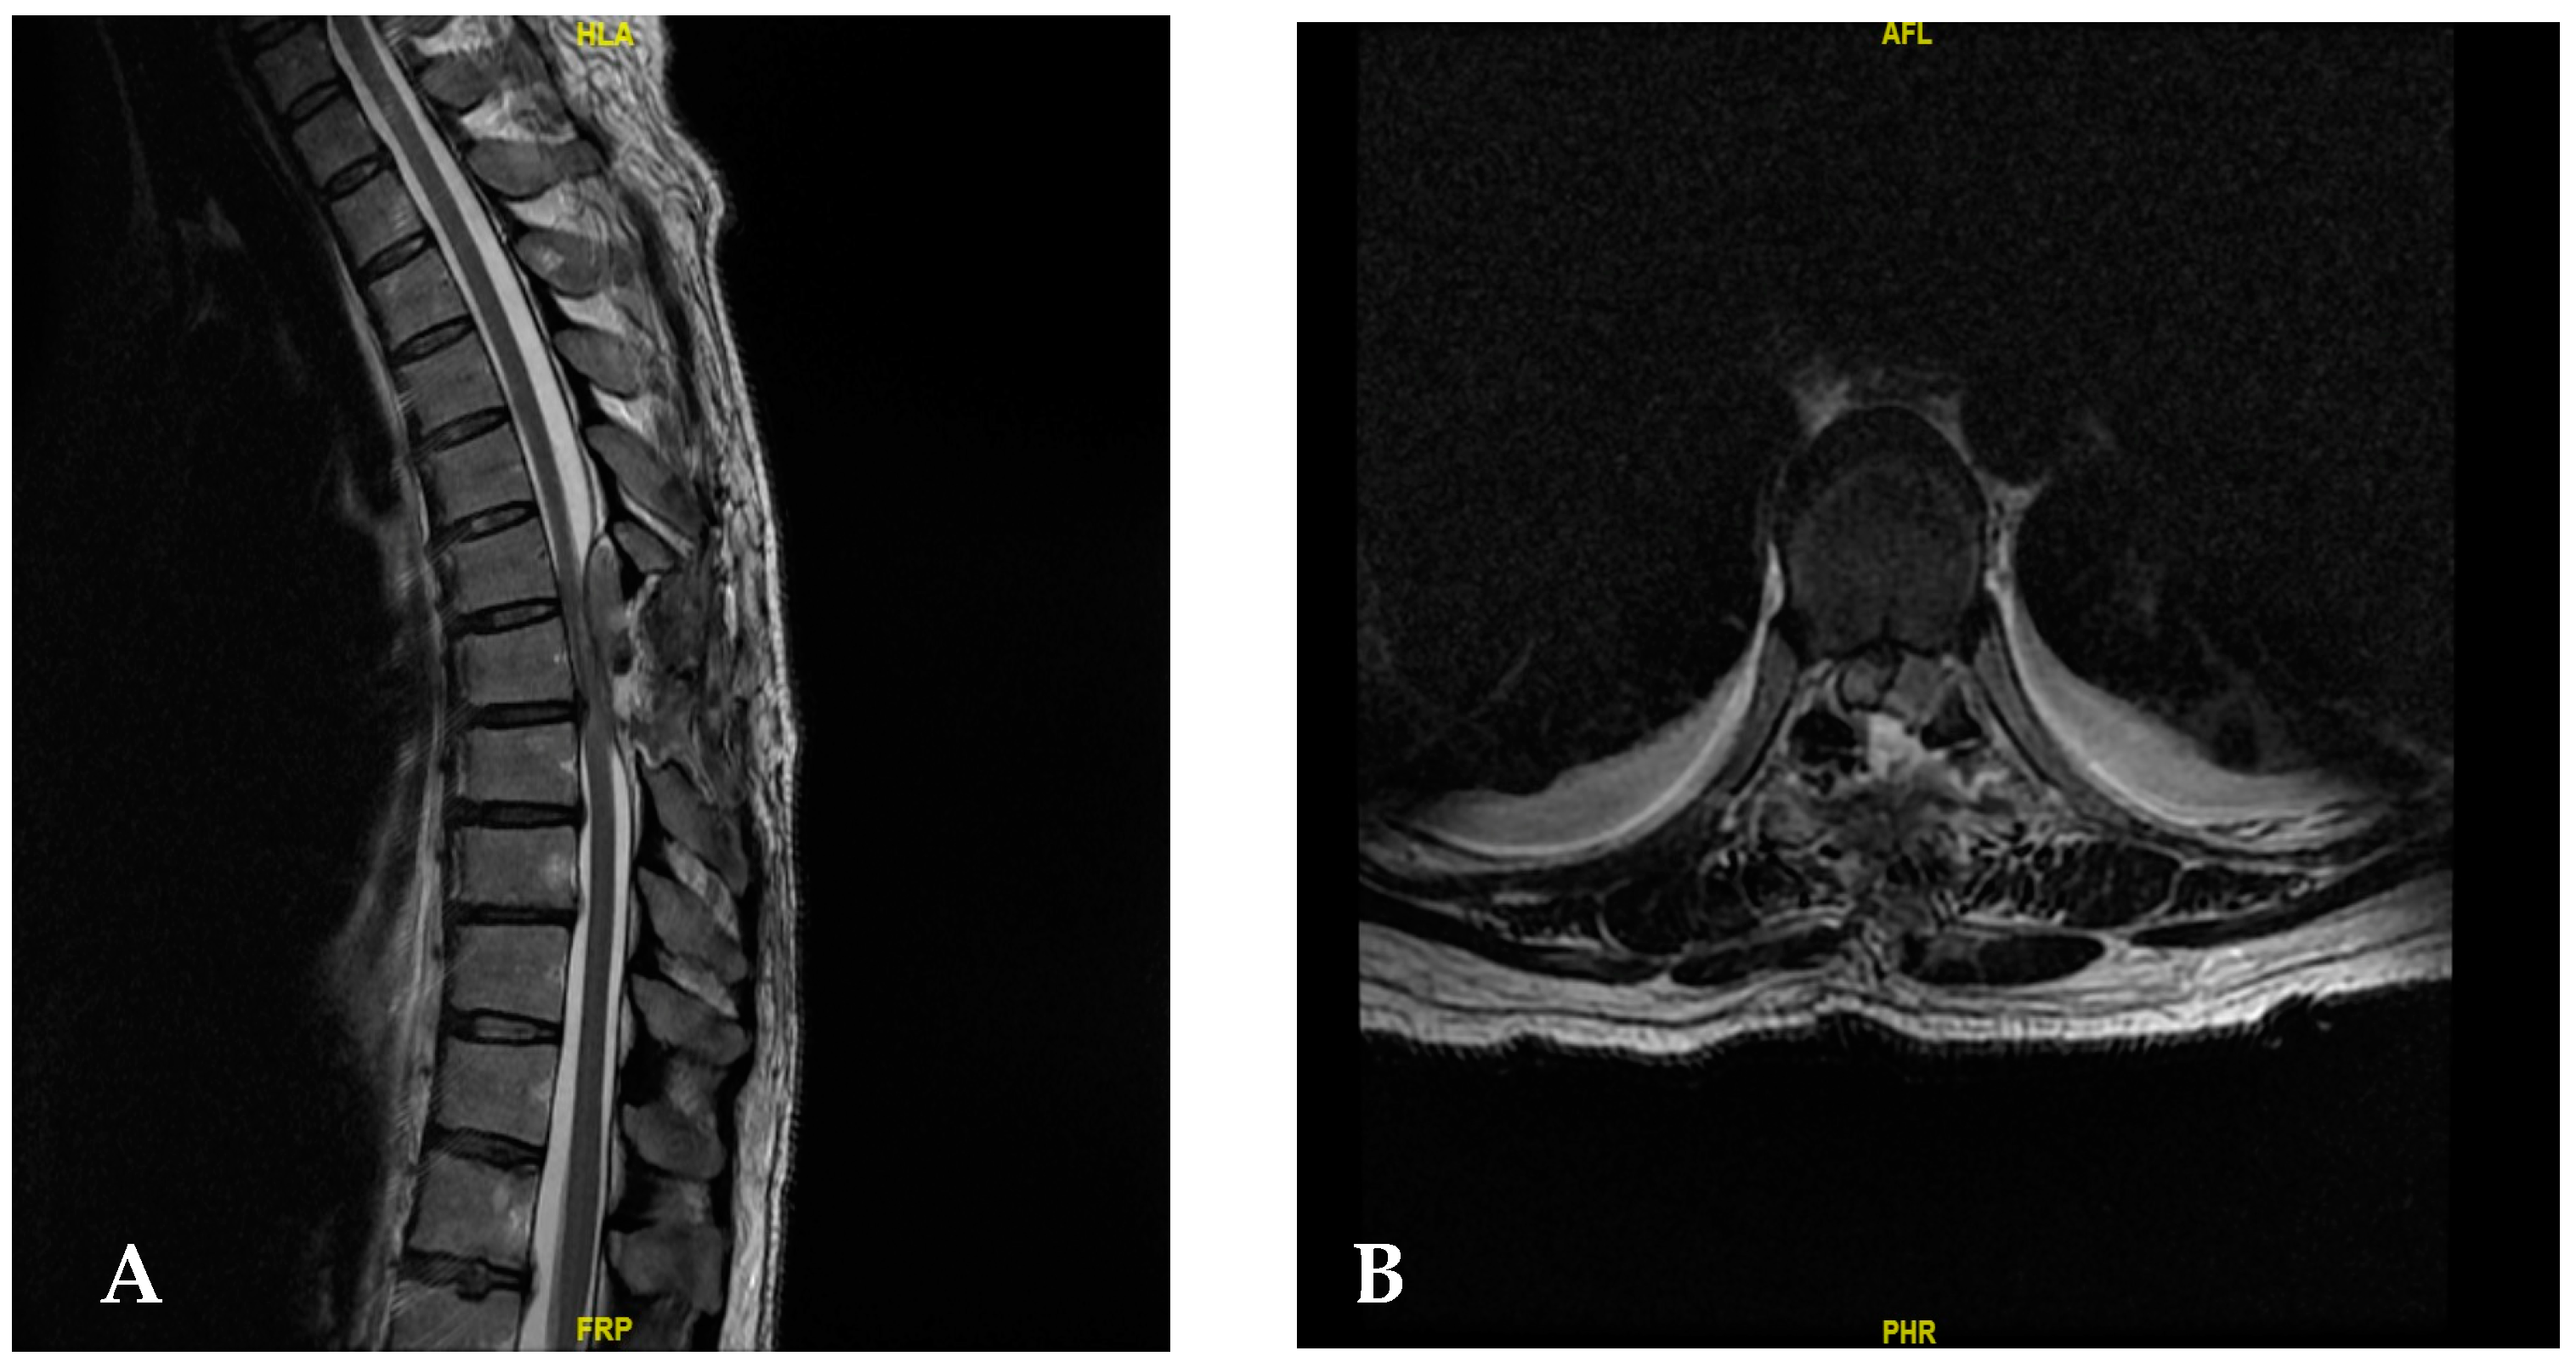

2. Case Presentation